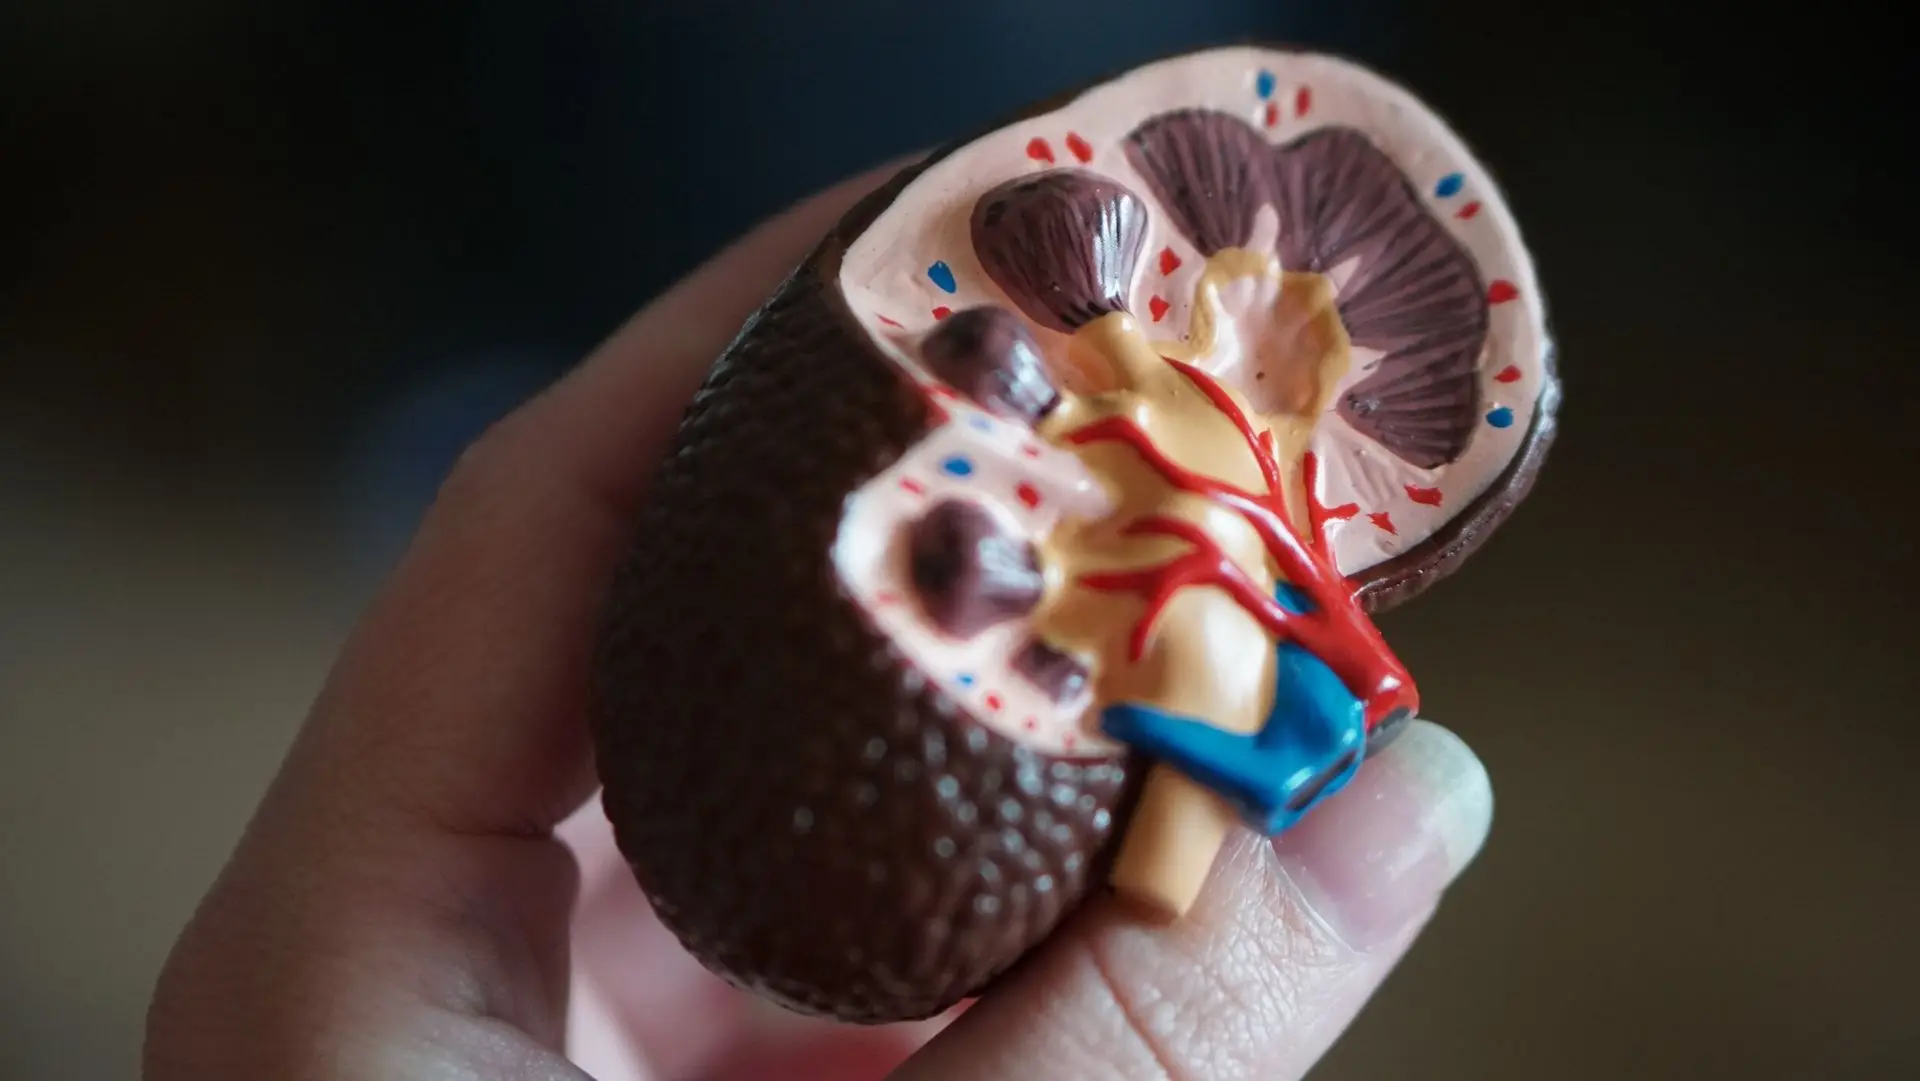

Chronic Kidney Disease

Chronic Kidney Disease gradually impairs kidney function, leading to health complications. Participation in clinical research not only provides you with compensation but also grants access to state-of-the-art healthcare services at no cost. These studies are an avenue to potentially benefit your own health while aiding in the advancement of kidney disease treatments. Interested individuals are encouraged to click below to register interest in joining upcoming trials.

Focal Segmental Glomerulosclerosis (FSGS)

FSGS causes scarring in the kidneys, which can lead to protein loss and kidney failure. Clinical research is vital for discovering effective treatments. Patients participating in studies can gain access to cutting-edge therapies. Interested individuals are encouraged to click below to register interest in joining upcoming trials.

Membranous Nephropathy

Membranous Nephropathy involves damage to kidney filters, leading to protein leakage into urine and potential swelling. Clinical research plays a crucial role in advancing treatment for such conditions. By participating in clinical trials, patients can access new therapies that may improve their health outcomes.Interested individuals are encouraged to click below to register interest in joining upcoming trials.

Proteinuric Kidney Diseases(PKD)

PKD is where excess protein is lost in urine, can indicate kidney damage. Joining these studies offers access to cutting-edge healthcare at no cost and includes financial compensation. Clinical research can be a way to potentially manage or improve your condition while helping advance medical knowledge. Interested individuals are encouraged to click below to register interest in joining upcoming trials.

IgA Nephropathy

IgA Nephropathy, characterized by IgA protein buildup in kidneys, can cause inflammation and impede kidney function. Our clinic is conducting 3 studies on this condition. Participating in clinical research means receiving top-tier medical care without any cost and being compensated for your time. It's an opportunity to potentially improve your condition and contribute to groundbreaking medical research. To take part in this vital research, please click below to apply.